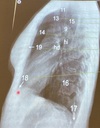

2

3

4

5

Perfectly

Q